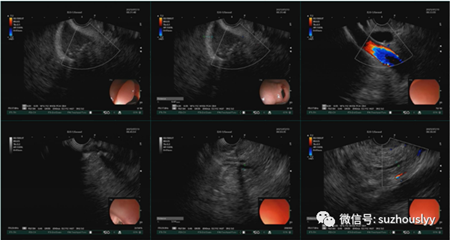

培训现场,王东教授操作过程中边演示边讲解,为一名反复腹痛患者完成超声内镜(大超)检查进而明确了腹痛病因,建议抗炎保肝对症处理后行ERCP取石术,择期行胆囊切除术。此次学习理论与实战结合、规范与进展并举,达到了开阔思路、提高理论水平及操作能力的效果,让参培人员收获颇丰。

近年来胆胰系统疾病的影像学检查发展迅速,除CT、MRI、体表超声等传统影像学检查外,超声内镜(EUS)取得良好效果,在胆胰疾病诊断中发挥重要作用。EUS是将超声微探头安置在内镜顶端,在内镜进入消化道观察消化道黏膜的同时进行超声扫描以获得消化道层次以及周围邻近器官的超声图像,当内镜进入十二指肠球部后由于探头临近胆囊及胰腺,故能显示胆胰疾病。超声内镜对于常规检查无法发现的胆胰管小结石和或微小结石有着独特的诊断价值。